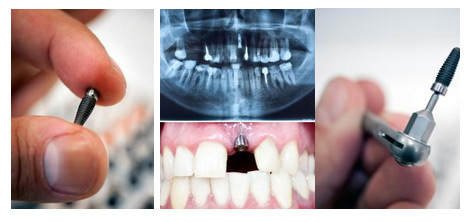

2、关于种植体,要认准国家注册证号!

目前,市面上种植体有欧美进口的,也有来自韩国、以色列等国家的。那么该怎么选择合适的种植体系统呢?

康贝佳口腔种植医师指出,种植体是三类医疗器械,目前国家准入的进口种植体有40个。因此只要是有国家批准注册证的种植体都是安全,可以放心使用的。不过,由于各个种植体的品牌、厂家、处理工艺的不同,价格有高有低。

专家还建议,选择种植体时,可以根据自己的经济状况,挑选世界排名相对靠前的种植体,质量更有保障。